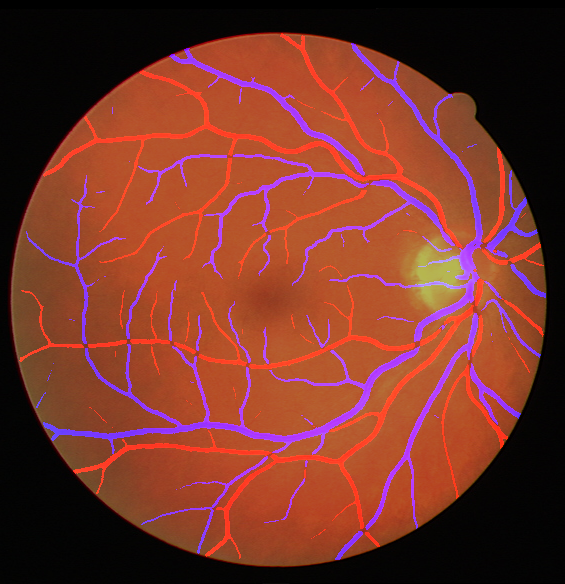

III The RAVIR Dataset

Recently there has been a substantial increase in the utilization of single wavelength confocal imaging that only captures reflected light passing through a pinhole, which will allow capturing high quality, high contrast fundus images. The images in our RAVIR dataset were captured using infrared (815nm) Scanning Laser Ophthalmoscopy (SLO), which in addition to having higher quality and contrast, is more convenient for the patient and is less affected by opacities in optical media and pupil size. This imaging modality is also commonly used in ophthalmology clinics. The RAVIR dataset consists of 46 IR retinal images from the UCLA Stein Eye Institute imaging database, divided into train and test sets of 26 and 20 images, respectively. We used 4 images from the 26 test images as our validation set. The images were captured using a Heidelberg Spectralis camera with a FOV. They are sized at pixels and compressed in the Portable Network Graphics (PNG) format. Each pixel in the images has a reference length of 12.5 microns. Table I compares our RAVIR dataset against other retinal vessel segmentation datasets.

Manual pixel-wise annotations were performed and verified by our experienced retinal image analysis specialist. Per-pixel labels were applied to all vessel regions that could accurately be identified as artery or vein. Vessels were labeled over the ONH in those images where the arteries and veins could be resolved. However, for images in which the veins and arteries over the ONH were indistinguishable, the ONH region was blocked for masking.

As reported in Table IV, we compared the SegRAVIR model against competing deep learning-based segmentation approaches on the RAVIR dataset. Evidently, SegRAVIR outperforms these methods as judged by all metrics for artery and vein classes with a healthy margin. In terms of Dice score, SegRAVIR outperforms CE-NET, IterNet and AG-Net by , and for artery segmentation and by , and for vein segmentation, respectively. Fig. 4 presents a qualitative comparison of the semantic segmentation outputs of SegRAVIR, CE-Net, and U-Net. Specifically, SegRAVIR yields more accurate vessel topology (i.e., thickness and orientation) segmentation with higher pixel-wise classification accuracy.

Table V presents quantitative performance benchmarks of SegRAVIR and other competing approaches for retinal artery and vein classification on the RITE dataset [11]. SegRAVIR outperforms previous state-of-the-art approaches in terms of accuracy, sensitivity, and specificity. Fig. 5 provides a qualitative comparison between segmentation outputs of SegRAVIR and the method of Hemelings et al. [40] on the RITE test set.

Using the final pretrained student SegRAVIR model in our knowledge distillation framework described in Section IV-D, we fine-tuned and tested the network on three publicly available datasets of color images, DRIVE [10], STARE [9], and CHASE_DB1 [12]. Fig. 7 shows example of SegRAVIR segmentation outputs on DRIVE and CHASE_DB1 datasets. Table VII presents a quantitative comparison between the segmentation performance of our SegRAVIR model and state-of-the-art models: R2U-Net [25], DU-Net [26], and IterNet [34]. By all evaluation metrics, SegRAVIR has achieved new state-of-the-art results on the DRIVE, STARE [9], and CHASE_DB1 datasets.